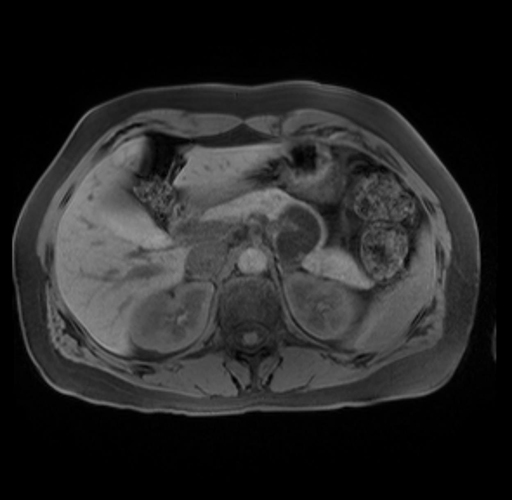

Imaging Analysis

Look through the patient's CT scan to identify any areas of concern for the necessary procedure.

Based on your CT findings, which issue(s) are present and would give reason for "planned slowing down moment(s)" in this case?

Considering a standard distal pancreatectomy procedure, what step(s) of the operation would you do differently in this case?